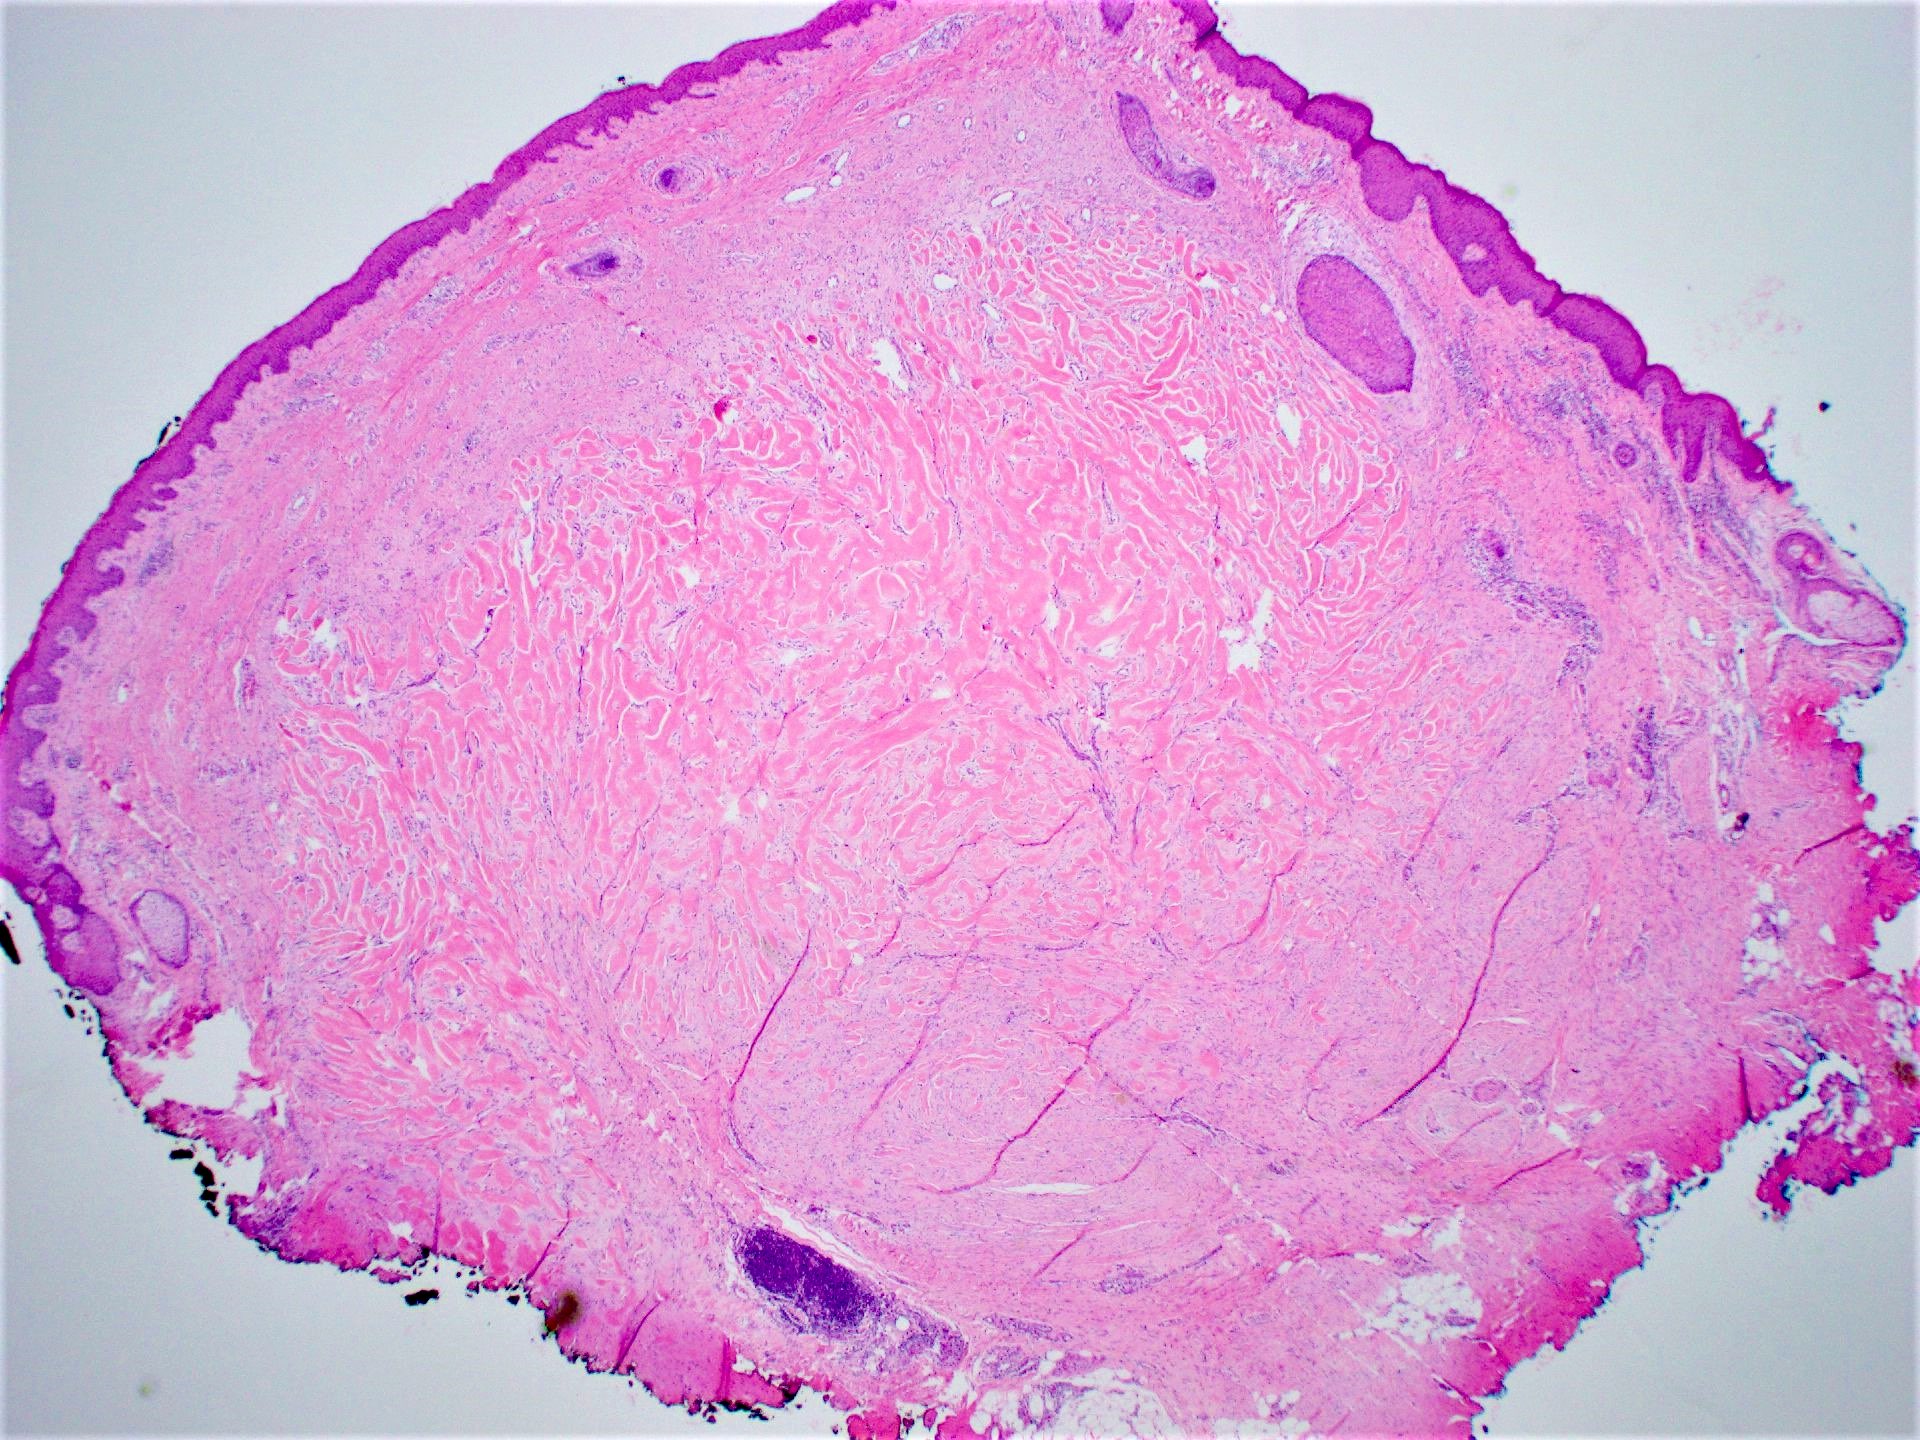

Microscopic (histologic) description

- Lesion of the deep dermis; sparing of papillary dermis (Am J Dermatopathol 2004;26:379)

- Characteristic long, broad, closely packed collagen bundles that stain uniformly eosinophilic (keloidal collagen) arranged in haphazard fascicles (Scars Burn Heal 2021;7:2059513120980320)

- Fibroblasts are increased compared to normal skin (Front Cell Dev Biol 2020;8:360)

- May appear edematous due to increased dermal mucosubstances (J Zhejiang Univ Sci B 2022;23:699)

- Tongue-like advancing edge (Front Cell Dev Biol 2020;8:360)

- Epidermis may be normal, thin or thick (most) and may be affected by secondary changes (such as hypertrophy and inflammation due to irritation / scratching) (Front Cell Dev Biol 2020;8:360)

- Lesion replaces adnexal structures (i.e., hair follicles and sweat glands) (Histol Histopathol 2015;30:1033)

- Fewer capillaries and blood vessels than surrounding skin (J Plast Surg Hand Surg 2010;44:272)

- Tend to have marked inflammation in the dermis at the leading edge of growing keloids (Scars Burn Heal 2021;7:2059513120980320)

- Overlap with hypertrophic scar and therefore correlation with the clinical features is recommended

Microscopic (histologic) images